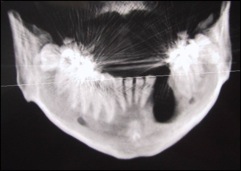

soit au niveau des maxillaires supérieurs à l'intérieur du sinus maxillaire (intervention appelée : "soulevé ou greffe de sinus") comme cela :